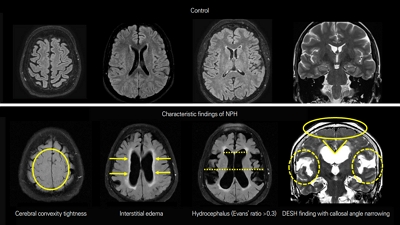

- Glymphatic System of the Brain: Anatomy, Physiology, and Clinical Implications

- Min Young Chun, Seok Jong Chung, Seong Ho Jeong

- J Korean Neurol Assoc. 2026;44(1):8-21. Published online February 1, 2026